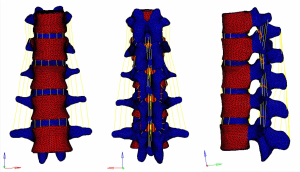

Meshing and supplemental establishment of the intervertebral disc and ligament: the three-dimensional entity models of T11–L3 and screw-rod system established in SolidWorks were imported into HyperMesh. Using the powerful mesh-making and dissection function of HyperMesh, a tetrahedral mesh was generated for the assembly, and 1-mm-thick cortical bone was constructed at the same time. The mesh sizes were 2 mm for T11–3 and 1 mm for the screw-rod system. Then, the structures of the endplate, annulus fibrosus, nucleus pulposus, anterior longitudinal ligament, posterior longitudinal ligament, intertransverse ligament, supraspinous ligament, interspinous ligament, ligamentum flavum, joint capsule ligament, and superior and inferior articular process cartilage were supplemented according to the anatomical site and shape to obtain a three-dimensional finite element model of T11–L3, which consisted of 191,386 elements and 55,741 nodes (the nodes and elements of T11–L3 Model Figure 10).

A three-dimensional finite element model of T11–L3 with the screw-rod system was obtained after the screw-rod system was added; it consisted of 310,970 elements and 73,469 nodes (the nodes and elements of T11–L3 Model with Pedicle Screw System Figure 11).